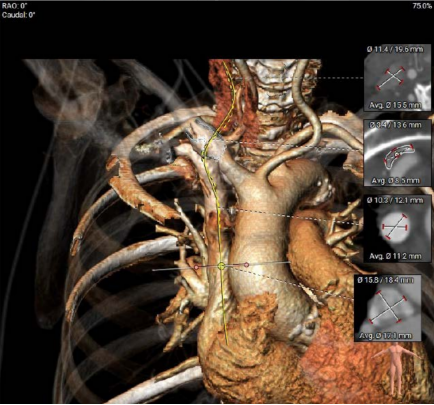

术前评估是本例成功实施的重要基础。患者接受多层螺旋CT(MSCT)检查,对三尖瓣环进行三维重建与精确测量,以评估解剖适配性,并选择合适型号(30–45 mm)的人工瓣膜。